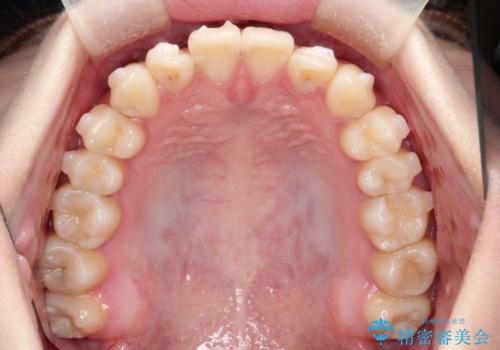

- 上下の前歯に捻れ(捻転)とガタつき(叢生)が見られます。

上の2番目の前歯の捻れに関しては、元々歯の大きさが小さい歯であるため、マウスピースにて力がかかりにくく、捻転の改善が一般的に難しくなりがちです。

マウスピース枚数 初回33枚 +追加22枚 +追加31枚

概ね2年で治療完了しました。

マウスピース矯正の特性として動かすのが難しい歯を含むケースでしたが、当院独自の工夫を随所に盛り込み、狙い通りの治療結果が得られました。